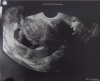

Gratuluję dziś wszystkim co miały wizyty i usłyszały serduszka ❤ oby jak najwięcej taj pięknych wiadomości. A to moje małe kropki.

2 kropki 😍 🥰 🥰 cudownie :)

Gratuluję dziś wszystkim co miały wizyty i usłyszały serduszka [emoji3590] oby jak najwięcej taj pięknych wiadomości. A to moje małe kropki.